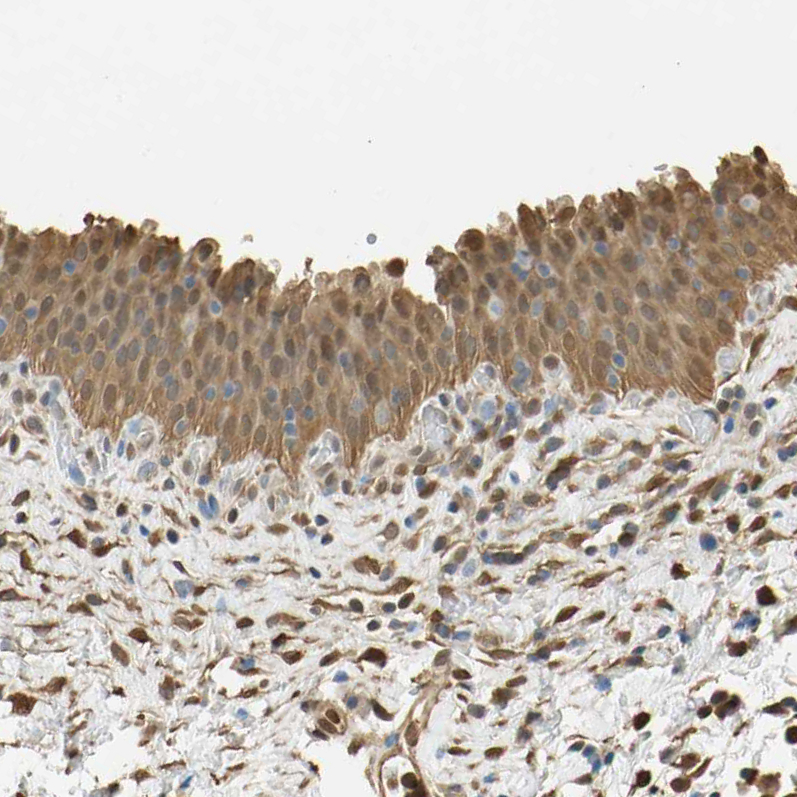

Immunohistochemical staining of human urinary bladder shows moderate cytoplasmic and nuclear positivity in urothelial cells.